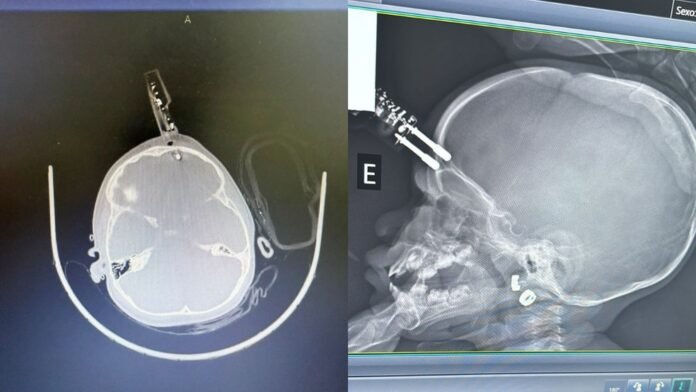

A criança foi inicialmente atendida na UPA de Divinópolis, e devido à gravidade do ferimento foi transferida pelo Samu para a sala vermelha do Hospital São João de Deus, referência na cidade. Exames de imagem mostraram que o objeto havia atravessado o osso craniano — muito fino nessa idade — e lesionado a parte externa do cérebro.

Imediatamente encaminhada ao centro cirúrgico, a menina passou por uma cirurgia de emergência para a retirada do carregador, controle de sangramento e correção da lesão. O neurocirurgião responsável, Bruno Castro, informou que o procedimento transcorreu sem intercorrências e a paciente acordou bem da anestesia.

Após 36 horas em observação intensiva, sem sinais de sangramento intracraniano em tomografias de controle, a criança foi transferida para a enfermaria e recebeu antibióticos intravenosos por cinco dias para prevenir infecções — um dos maiores riscos em casos com corpo estranho penetrando o crânio.